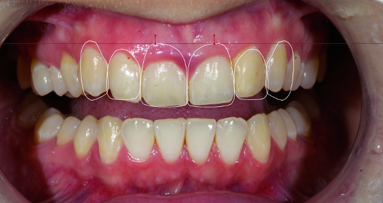

The patient presented to a dental specialist group practice at a private hospital setting with complaints of frequent pain, swelling and pus discharge from the right maxillary central incisor region (FDI Notation #11). He also complained about the aesthetics of the fixed partial denture and, in particular, the length, opaqueness, and proclination of the incisors and the colour of the ceramics (Fig. 1). His dental history revealed that tooth #11 was extracted approximately three years prior. A 3-unit fixed partial denture utilising #12 and 21 as abutments was subsequently fabricated. Six months later, pain and swelling of the region at #11 and 12 was noted. Endodontic treatment was performed on #12 and a new 3-unit all-ceramic fixed partial denture was re-fabricated. The symptoms had persisted despite these interventions.

An oral examination revealed a localised swelling in the #11 region with a discharging sinus (Fig. 2). The abutment teeth #12 and 21 were not tender to percussion. A radiographic examination revealed a well circumscribed radiolucency with a well-defined border in the region of #11 measuring 1 cm by 0.5 cm. The radiolucency was mesial to the root of #12. A small radiopaque mass was observed within the radiolucency. Tooth #12 had an adequate endodontic filling with small periapical radiolucency (Fig. 3).

Figs. 1–4: Pre-treatment lower facial view (Fig. 1). Poor aesthetic of the existing fixed partial denture (Fig. 2). Pre-treatment panoramic radiograph. Note the radiolucency over the maxillary right central incisor (Fig. 3). Placement of Replace Select tapered implant (Fig. 4).